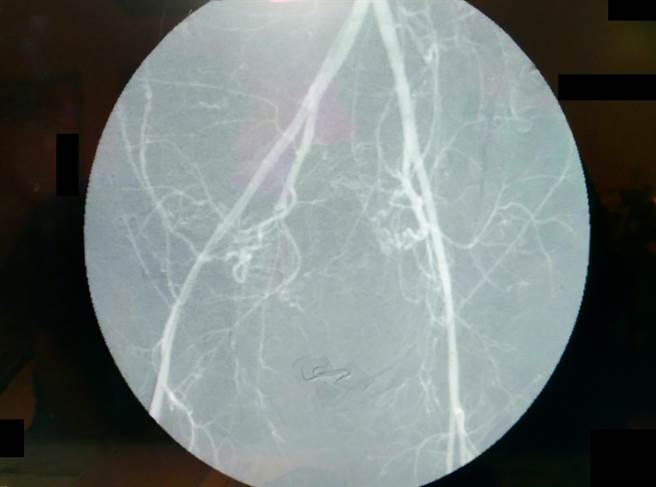

周志恒主任表示,透过放射线仪器,可清楚呈现骨盆腔血管,让医师执行血管栓塞,帮助产后大出血的产妇及时止血。(大千医院提供/谢明俊苗栗传真)

周志恒指出,过去产后大出血的治疗方式会先给予药物及输血,但若效果不佳,产妇可能面临子宫摘除的情形,虽能及时保住性命,但日后则无法再生育。现行动脉导管栓塞术可透过放射线仪器,让错综复杂的血管清楚呈现,医师在手术时更容易治疗,帮助产妇在短时间内大幅减少出血量。